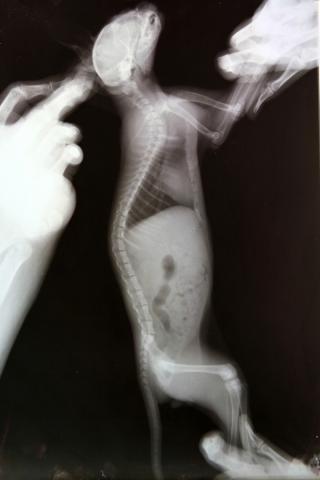

Здравствуйте. У меня приёмный котёнок-подобрашка. Был подобран на улице девушкой волонтёром в первых числах августа, примерно в 2-х месячном возрасте. У котенка расстройства координции. Светлана сделала котёнку рентген, на котором выявлено повреждение 1 шейного позвонка. Первично было назначено: пирацетам, ловетта, фуросемид; далее добавлены мильгамма, преднизолон. Переназначение от другого врача: Мильгама, Нейромедин 0,3*2р/д 15 дней. Курс Нейромедина проведён уже 2-х кратно. Улучшения незначительные, недолговременные. Нарушения координации выражются в треморе головы при малейшем возбуждении (бьётся носом об тарелку, когда кушает), дискоординация движения ног при ходьбе- спина не выпрямляется, задние ноги находят на передние- заваливается на бок, плохо развиты задние конечности, передние контролирует лучше. Планируем в ближайшее время МРТ. Какой отдел нам делать, посоветуйте. Буду рада любой информативной помощи. Спасибо! Это наши снимки.

Извините, как-то пропустила вашу тему. Снимки нечеткие, рассмотреть масштаб трагедии я по ним не могу, тем более снимки сделаны только в сагиттальной проекции, а хотелось бы увидеть и фронтальную.

Tella, Михаил Александрович! Очень благодарна вам за содержательные ответы!!!! Уточню, так как снимки выложены, действительно, не в очень хорошем качестве. Врач, наблюдающий Севу и назначивший нам последнее лечение увидел на снимке трещину на атланте. Где порекомендуете провести нам подобное исследование и возможную операцию? Специализируетесь-ли вы в этом направлении?

Лично я специализируюсь именно на этом направлении. Но про трещину на атланте - как то очень сомнительно. В таком, как у Вас, возрасте кости не ломаются, а, скорее, гнуться. И кости позвонков очень эластичны. Да и трещина если и есть, то что плохого? Трещина - это перелом без смещения. А раз нет смещния то в чем может быть проблема?